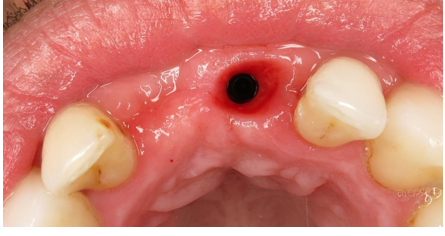

Extraction of the UR1

Single Implant placement UL1 for cantilever bridge